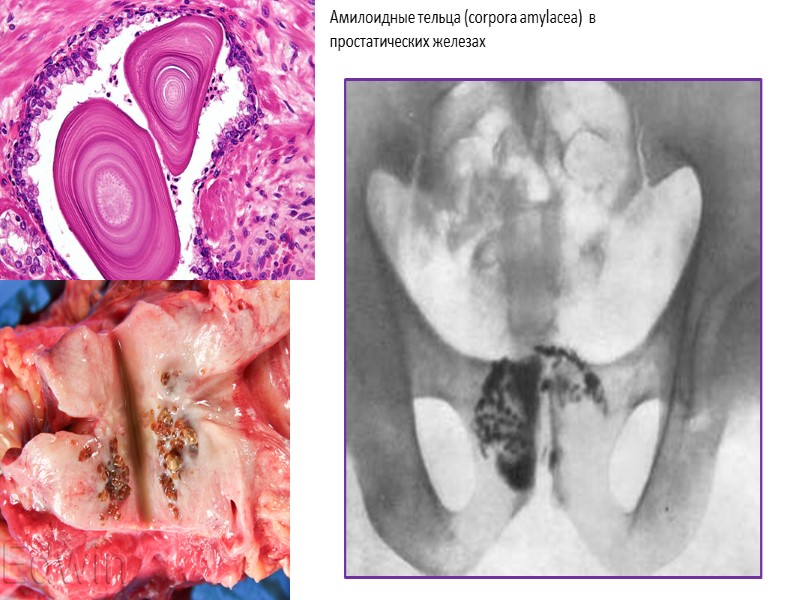

Амилоидные тельца (corpora amylacea) в простатических железах